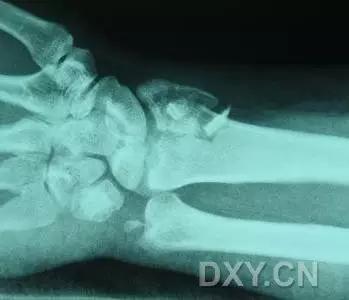

10. Rolando 骨折

第一掌骨基底的 T 或 Y 型粉碎性骨折,可伴有关节半脱位。

(来源:AO foundation)